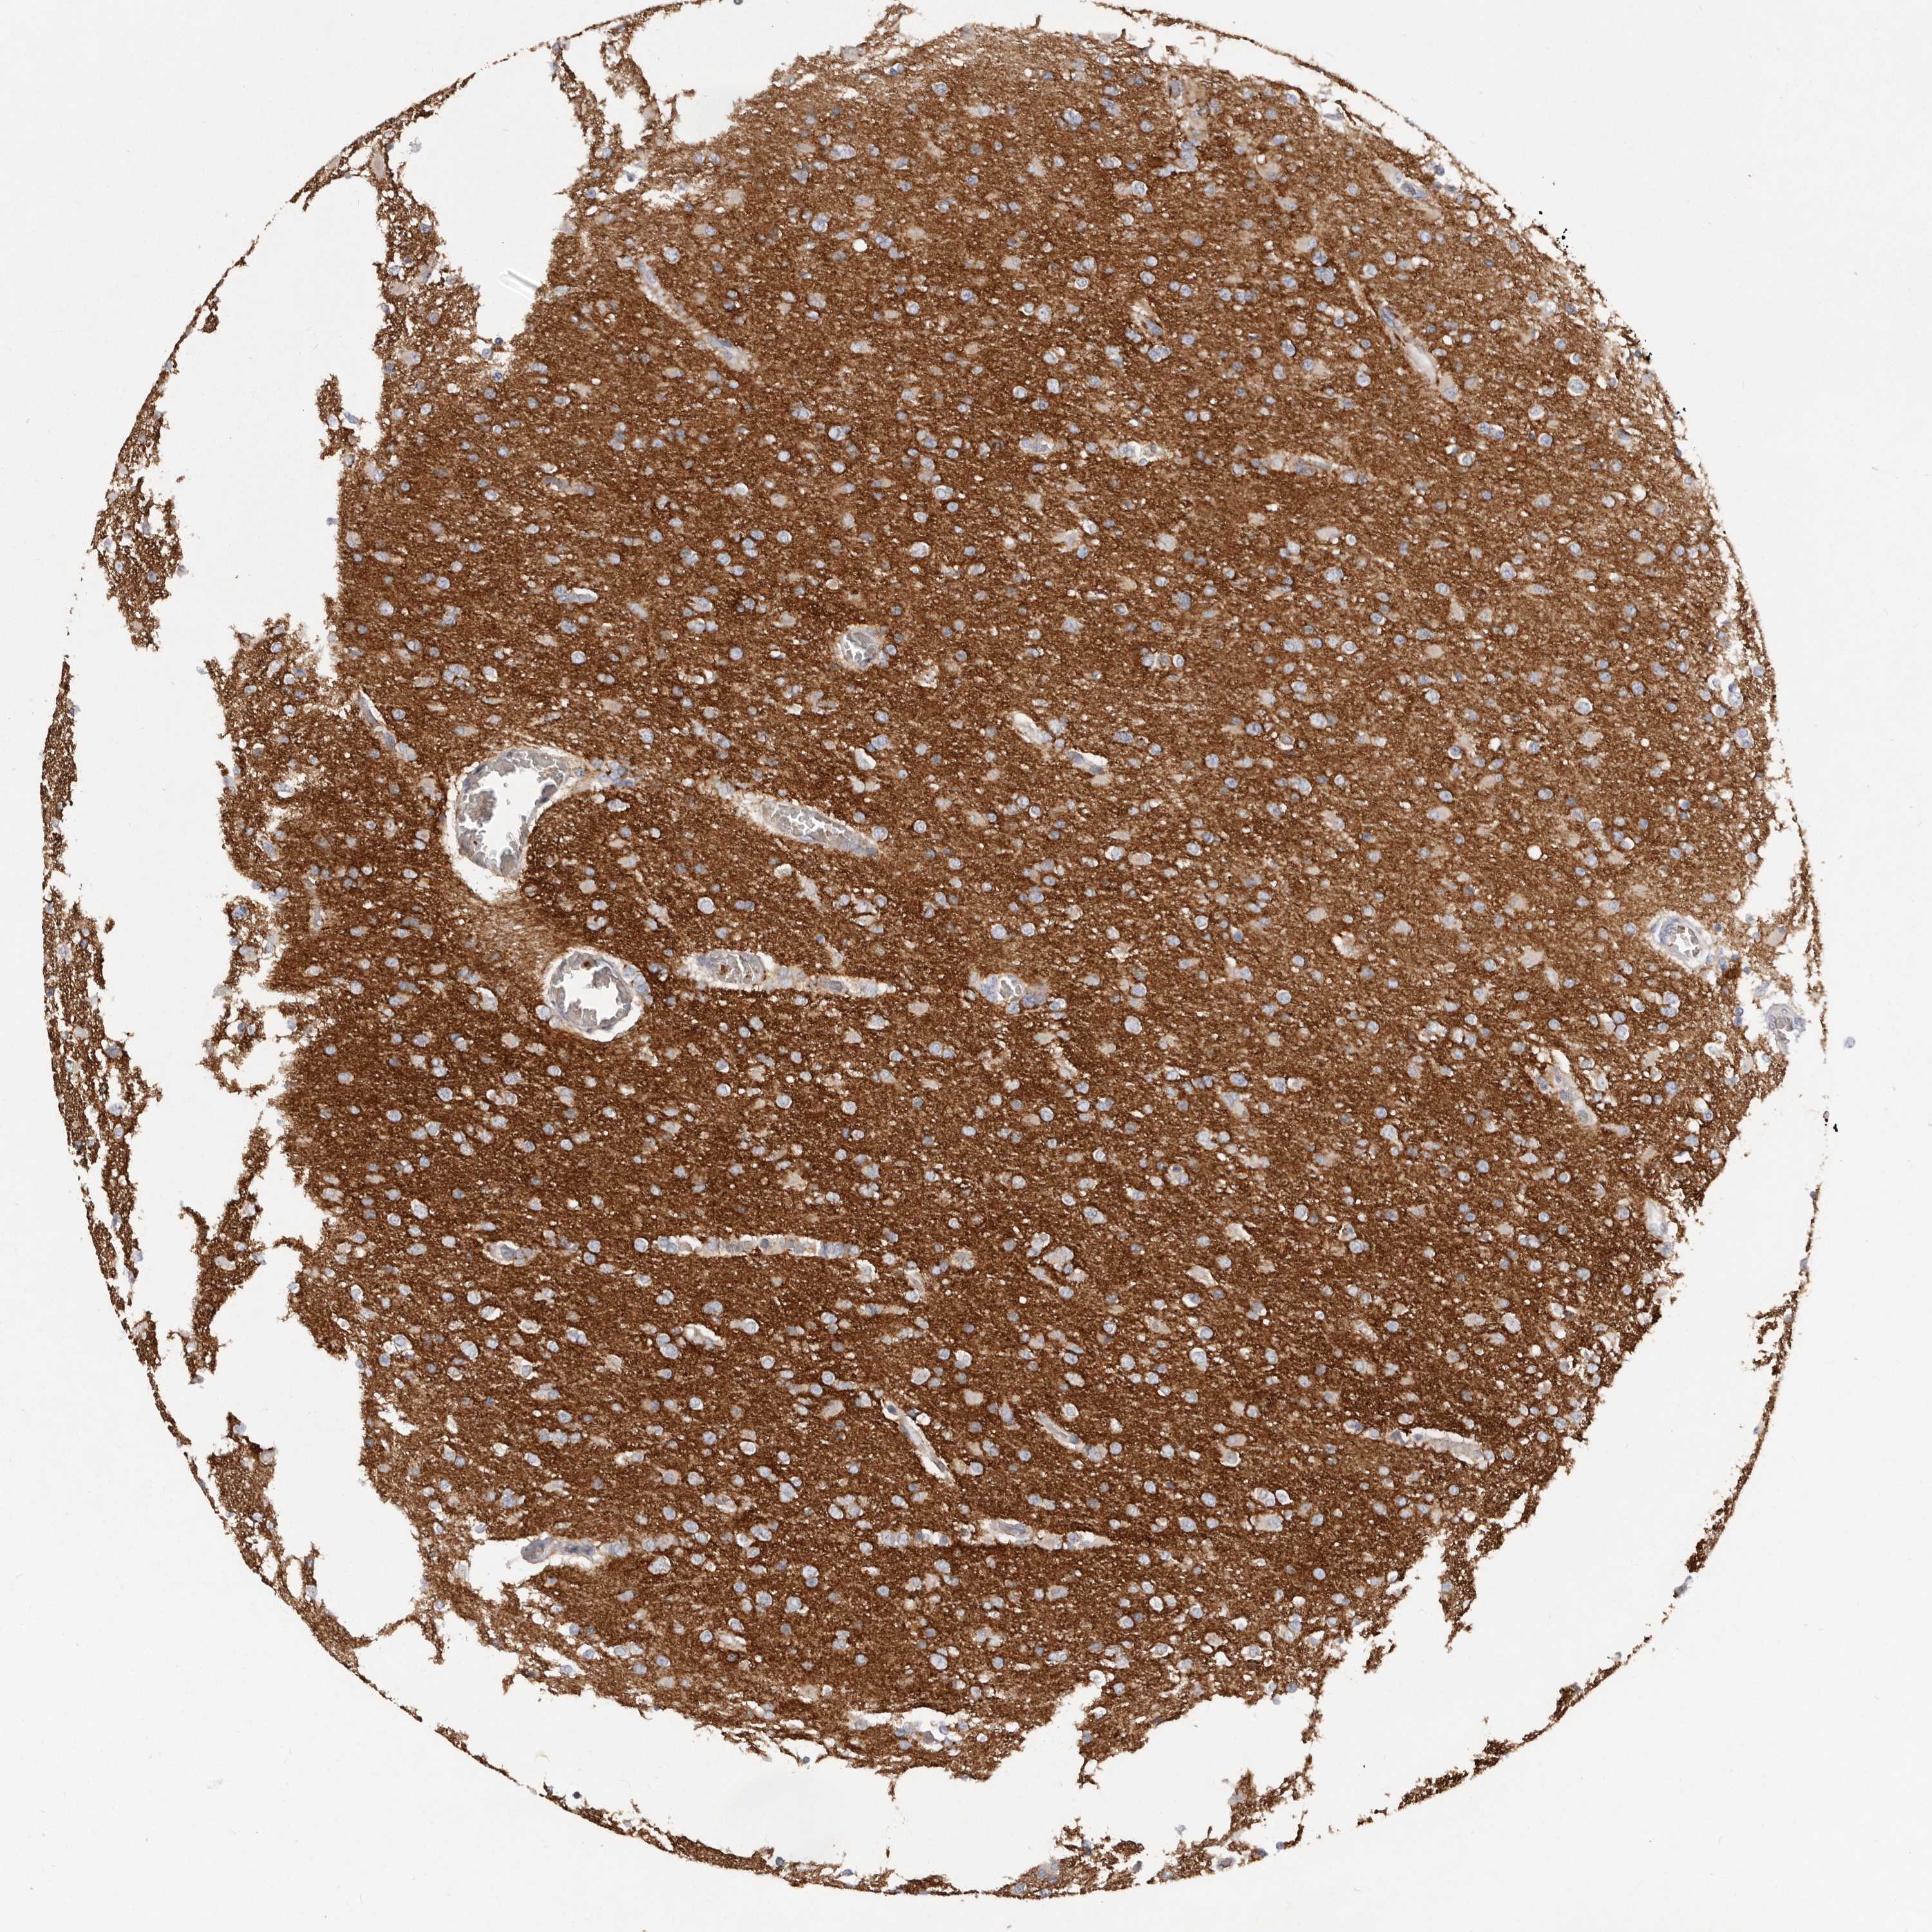

GLIOMA - Protein expressioni

A mouse-over function shows sample information and annotation data. Click on an image to view it in a full screen mode. Samples can be filtered based on level of antibody staining by selecting one or several of the following categories: high, medium, low and not detected. The assay and annotation is described here.

Note that samples used for immunohistochemistry by the Human Protein Atlas do not correspond to samples in the TCGA dataset.

Antibody stainingi

Antibody staining in the annotated cell types in the current human tissue is reported as not detected, low, medium, or high, based on conventional immunohistochemistry profiling in selected tissues. This score is based on the combination of the staining intensity and fraction of stained cells.

Each image is clickable and will lead to virtual microscopy that enables deeper exploration of all samples and also displays staining intensity scores, fraction scores and subcellular localization as well as patient and tissue information for each sample.

Antibody HPA027134

Antibody HPA027150

Antibody HPA029859

Antibody CAB022343

Staining

High

Medium

Low

Not detected

Intensity

Strong

Moderate

Weak

Negative

Quantity

>75%

75%-25%

<25%

None

Location

Nuclear

Cytoplasmic/membranous

Cytoplasmic/membranous,nuclear

Glioma, malignant, High grade

Glioma, malignant, Low grade

Glioblastoma, NOS